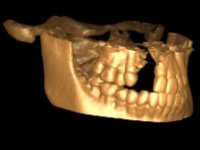

Root canal treatment was immediately performed on tooth 11. In the meanwhile, a CBCT scan was done to evaluate bone quality and quantity in the cleft area. The available bone was significantly reduced in vertical and horizontal dimensions. Due to the difficulty in performing a bone augmentation in this area, together with periodontal surgery to improve soft tissues, our treatment plan was the following: